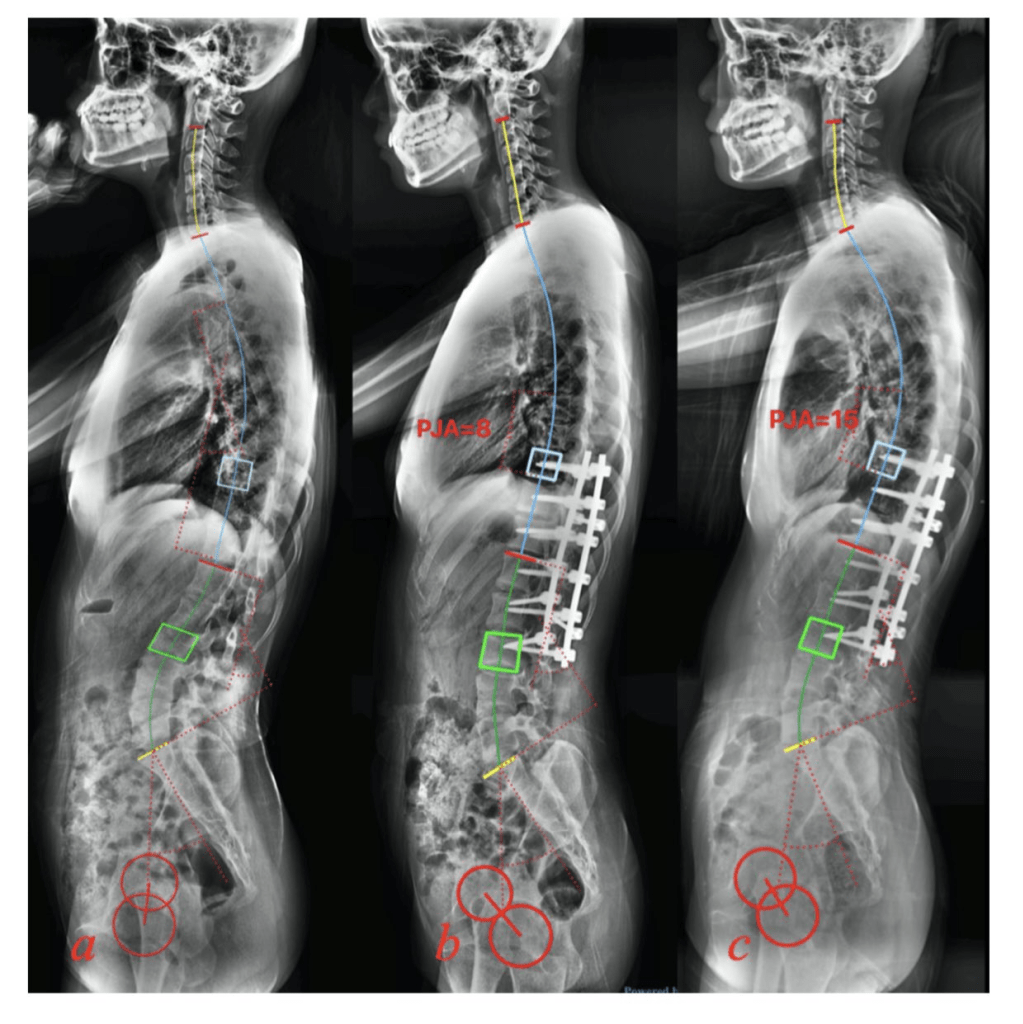

Este estudio tuvo como objetivo investigar la relación entre la incidencia pélvica y la morfología espinal sagital en la escoliosis idiopática adolescente (AIS) de Lenke 5 y su impacto en la tasa de cifosis de la unión proximal después de la cirugía.

La incidencia pélvica (IP) influye en la morfología espinal sagital en Lenke 5 AIS, aunque no muestra una relación inherente con la lordosis lumbar. El PI también se correlaciona con la tasa de PJK después de la cirugía.

Restaurar una relación ideal de incidencia pélvica posoperatoria (IP) -lumbar-lordosis (LL) podría disminuir la tasa de cifosis de la unión proximal (PJK).